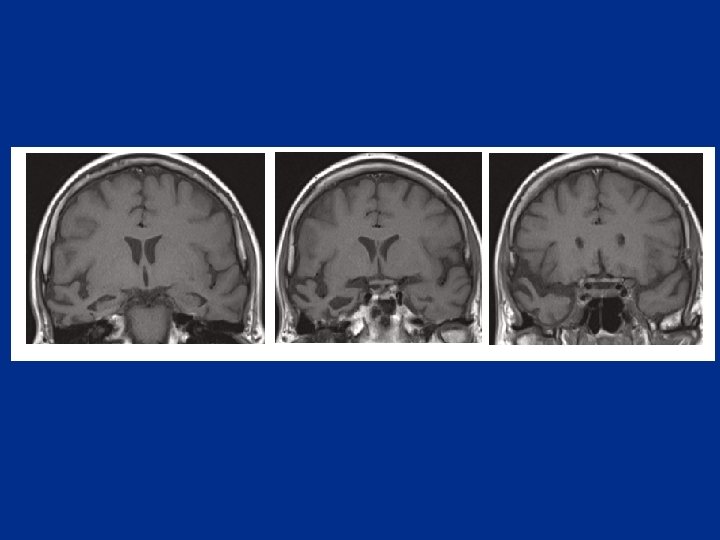

1 Qui est qui? 3 4 2 2 a-Maladie d’Alzheimer c-Démence Fronto Temporale b-Aphasie Primaire Progressive d-Démence

Qui est qui? 2 3 a-Maladie d’Alzheimer c-Démence Fronto Temporale b-Aphasie primaire progressive d-Démence

1 Qui est qui? 2 a-Maladie d’Alzheimer c-Démence Fronto Temporale b-Aphasie primaire progressive d-Démence

2 Qui est qui? a-Maladie d’Alzheimer c-Démence Fronto Temporale b-Aphasie primaire progressive d-Démence sémantique (Hodges Brain 2009)

Qui est qui? 2 4 a-Maladie d’Alzheimer progressive c-Démence Fronto Temporale b-Aphasie primaire d-Démence